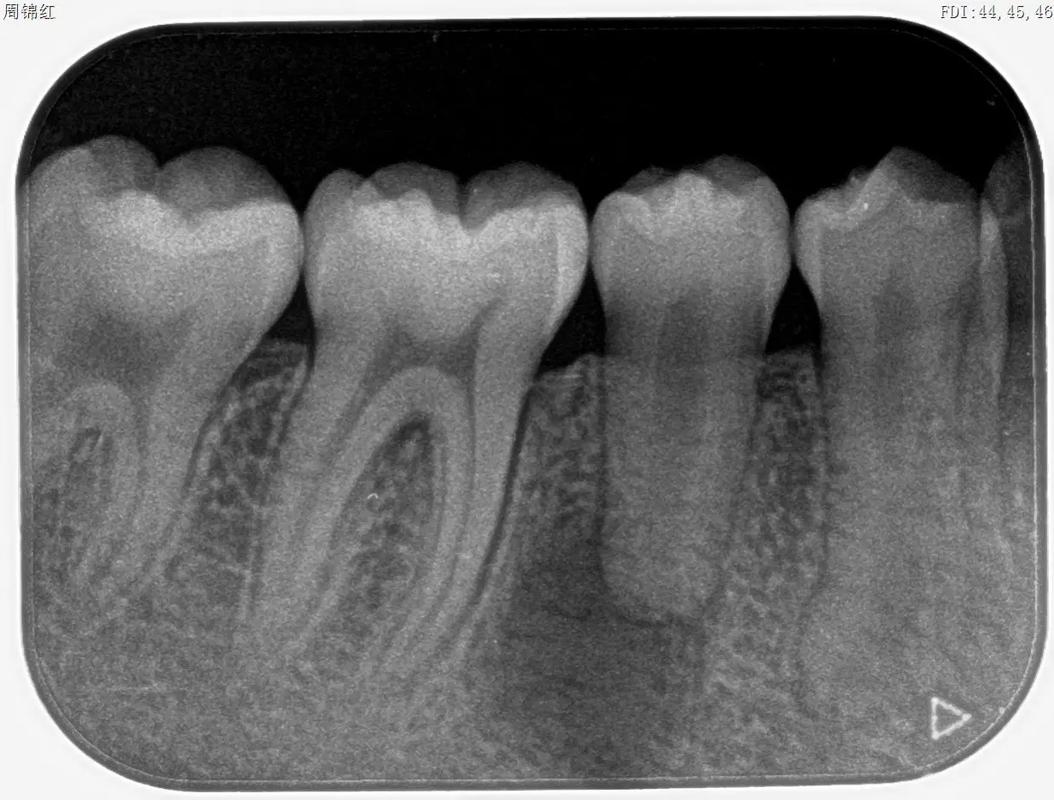

- 监测重点:每3个月拍摄根尖片,观察牙根长度变化、根尖孔形态及有无吸收迹象;临床检查牙齿松动度、叩痛,评估根尖周反应。

- 影像学检查:治疗初期拍摄根尖片、曲面断层片,评估牙根长度、形态;治疗中每6个月复查CBCT,三维观察根尖周骨密度、根尖孔形态及有无吸收;